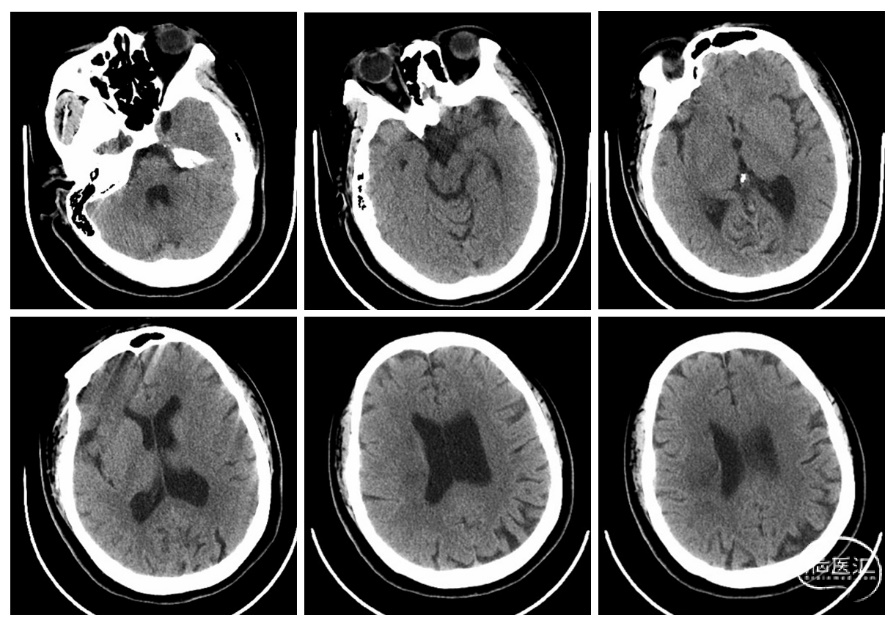

图1. 头颅CT提示右侧侧脑室旁低密度灶,考虑缺血梗塞灶。

患者,女性,16岁,因“头痛10天,左侧肢体无力8天,双目失明5天”入院。患者10天前因劳累、暴晒后突发头痛,为胀痛,有炸裂感,当地卫生院考虑“中暑”,予藿香正气水治疗,患者头痛无明显好转。8天前突发左侧肢体无力,至外院就诊,查头颅CT提示:右侧侧脑室旁可疑斑片状稍低密度灶,头颅CTA提示:右侧大脑中动脉M1段管壁毛糙、管腔狭窄、周围少许侧支形成、Moyamoya病待排,考虑“脑梗死”,予“阿司匹林100mg QD+氯吡格雷75mg QD”治疗,患者左侧肢体无力稍好转。5天前患者突发双眼视物模糊,迅速发展为双目失明,2天前行腰穿检查,测得初压为400mm H₂O,末压270mm H₂O,予“甘露醇20g Q12H+甘油果糖250mL Q12H”降颅压,患者症状未见好转,为进一步治疗来我院神经内科急诊就诊,拟“脑梗死、颅高压、双目失明”收住入院。自起病以来,神志清,精神软,胃纳睡眠欠佳,无大小便失禁,体重无明显减轻。既往无高血压、糖尿病、心脏病等基础疾病及手术外伤史。入院查体:体温:37.4℃,呼吸:14次/分,脉搏:136次/分,血压118/74mmHg,血氧饱和度:98%。肥胖面容,身高:165cm,体重:93Kg,体重指数(BMI):34.2kg/㎡。神清,对答切题,口齿清晰,右眼弱光感,左眼失明,双侧瞳孔等大等圆,直径6mm,直接和间接对光反射消失,鼻唇沟对称,伸舌居中。全身浅表淋巴结未及肿大。双肺呼吸音清,未闻及干、湿啰音,心律齐,心前区各瓣膜听诊区未及病理性杂音,腹平软,无压痛及反跳痛,肝脾肋下未及。双下肢无水肿,右侧肢体肌力V级,左侧肢体肌力IV级,感觉无明显异常,肌张力无亢进,左侧巴氏征阳性,右侧巴氏征阴性。辅助检查:我院头颅CT(图1)提示:右侧侧脑室旁低密度灶,考虑缺血梗塞灶。头颅MRI平扫+DWI(图2)提示:右侧颞叶及右侧脑室旁新近脑梗塞,附见空泡蝶鞍。头颅MRV(图3A)示:上矢状窦、窦汇,脑表浅静脉及下矢状窦可见,大脑内静脉、大静脉、直窦显影清,未见充盈缺损;双侧横窦局部稍窄。